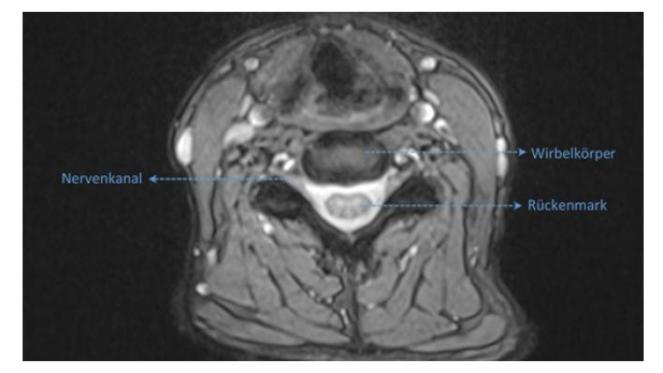

Bandscheibenvorfälle (NPP)

Bandscheiben sind flexible, faserknorpelige Verbindung, die als Stoßdämpfer zwischen den Wirbel dienen.

Mit zunehmendem Lebensalter kann es zu verschleißbedingten Rissen am äußeren Ring der Bandscheibe (Faserring) und zu einem Austritt des gallertartigen Kerns kommen. Dieser kann die benachbarten Nervenwurzeln oder das Rückenmark zusammendrücken und zu lokalen oder ausstrahlenden Schmerzen in den Armen und Beinen, ggf. auch mit Sensibilitätsstörungen und motorischen Ausfällen, führen.